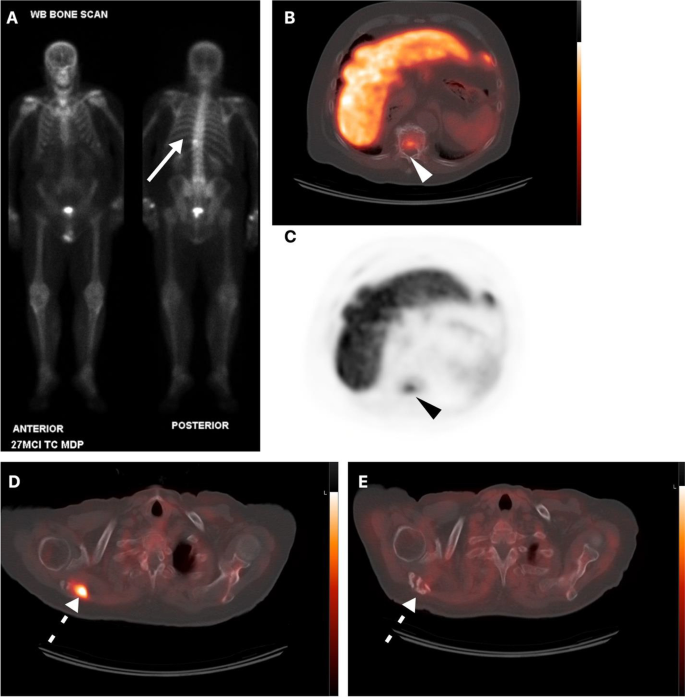

Management Impact Of Metachronous Oligometastatic Disease Identified On 18f Fluciclovine Axumin Pet Ct In Biochemically Recurrent Prostate Cancer Springerlink

True Positive Fluciclovine Pet Ct And False Negative Ct In The Prostate Download Scientific Diagram